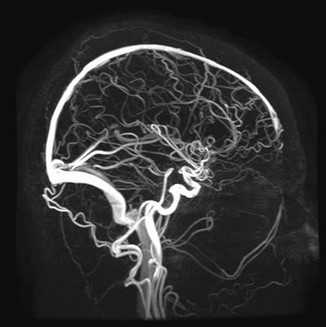

МР-ангиография церебральных артерий на аппарате тоннельного типа

Сканирование проводят в аксиальной, сагиттальной и фронтальной плоскостях. Для уточнения локализации патологического очага и перед операциями реконструируют 3D-модель рассматриваемой зоны.